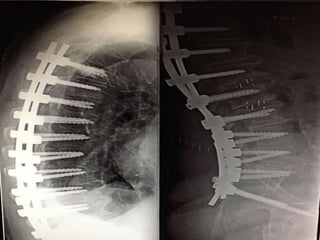

Εκφυλιστική κύφωση – σκολίωση ενήλικος

(+) Parkinson

Προσθία προσπέλαση

Autografts

Οπίσθια προσπέλαση

Πρόσθια – Οπίσθια

Διόρθωση και Σπονδυλοδεσία

15yrs F- up